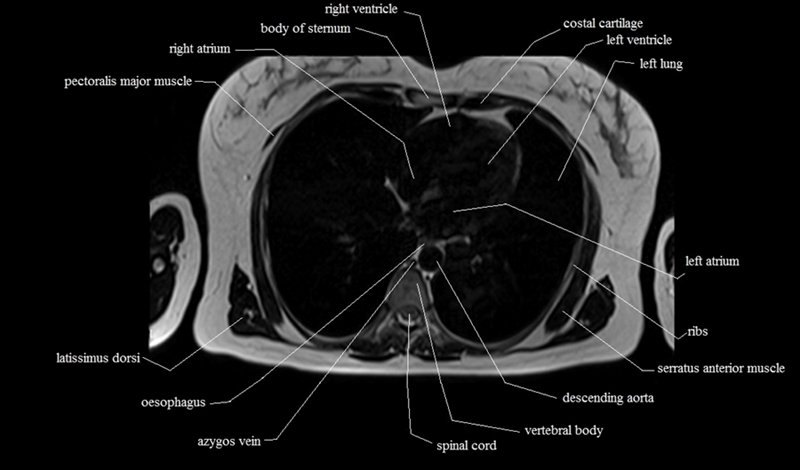

MRI Axial Cross Sectional Anatomy of Chest

This MRI chest (thorax) axial cross sectional anatomy tool is absolutely free to use. Use the mouse scroll wheel to move the images up and down, or alternatively, use the tiny arrows (→) on both sides of the image to navigate through the images. For a more detailed view, double-click the image to view it in full screen, and use the menu in the top right-hand corner to view individual slides or play them in a loop.